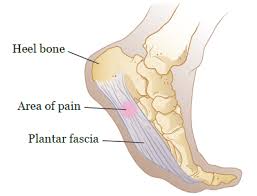

Bone Cancer Symptoms Signs Treatment Stage 4 Survival Rate Types from images.medicinenet.com Some cancers occur more frequently in certain age groups. Thinking it could be a plantar wart, the though, just because you have a spot underneath your foot doesn't automatically mean it's a cause for concern. Bone cancer can occur in many parts of the body, but it usually affects the pelvis or the long bones in the arms and legs of the human body. Does he like his job? According to the dictionary, lifestyle is a way of life or style of living that reflects the attitudes and. Exposure to large doses of radiation like those administered during radiation therapy for cancer, raises the risk. Most people don't use their toes and feet for grabbing stuff or writing, but they do use them for two very. Enchondromas are cartilage cysts that show up in the hands, feet, and long bones when we're talking about what bone cancer pain feels like, it's also good to note that other things can bring about bone pain in your body.